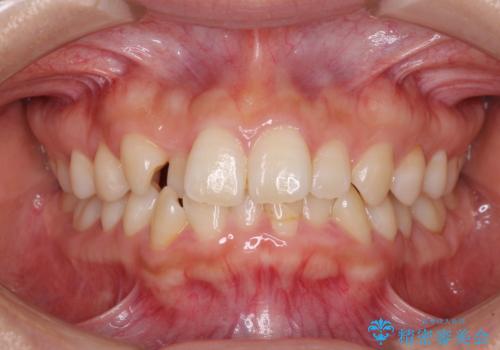

- 前歯のクロスバイトを気にして来院された患者様です。

治療方法としては、マウスピース矯正(インビザライン)でもワイヤー矯正でも、何でも対応可能ですが、自己管理の煩わしさがなく、治療期間の目処を立てやすい表側のワイヤー矯正にて治療を行うこととしました。